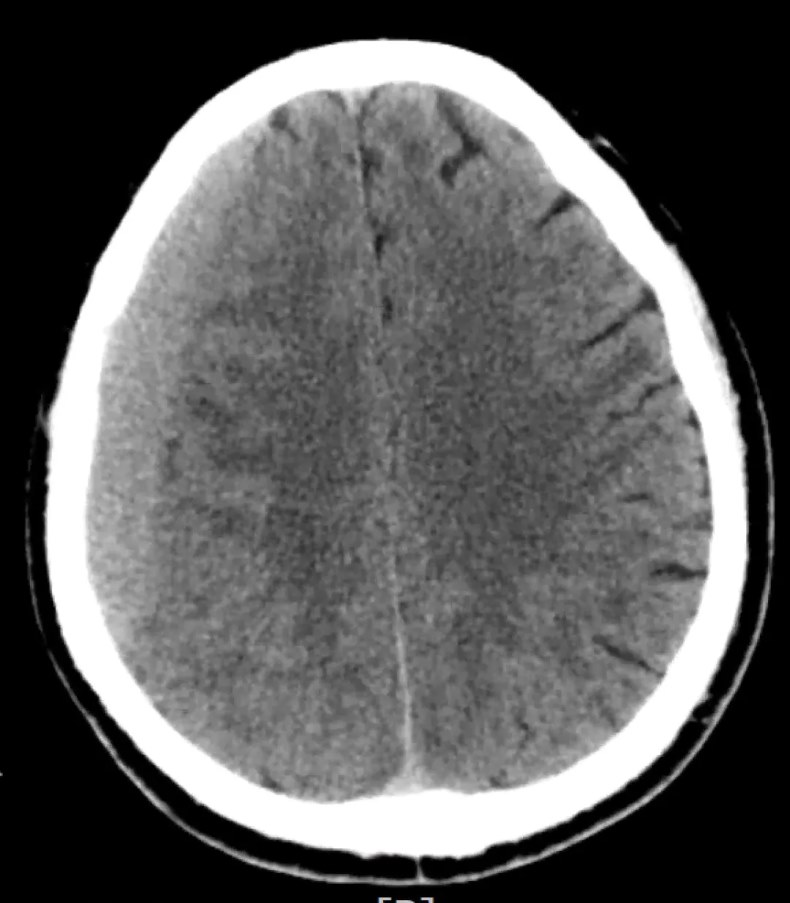

一个月前,83岁的陈阿公(化名)不小心摔了一跤,磕到了脑袋,但由于没有出现明显的头晕、头痛等症状,就一直没有到医院检查。可就在几天前,阿公的状况开始有点不对劲了,头闷闷的,有点痛,走路也没力气。家人赶紧把他送到温州医科大学附属第一医院急诊科就诊,急诊医生不敢大意,立刻安排阿公做了急诊头颅CT,检查结果提示:右侧慢性硬膜下血肿,这是颅内出血最为常见的类型之一,血肿量初步评估达到了三四十毫升。

▲ 慢性硬膜下血肿ct图